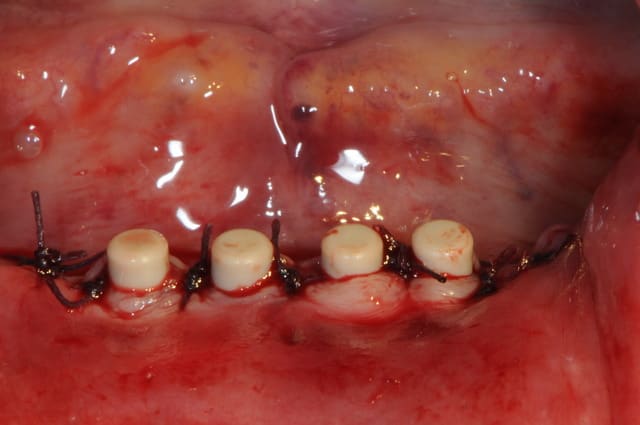

Bon, je viens de lui poser ses 4 mini-implants ce matin.(diamètre2.8 longueur 13mm)

je crois que comme ils ne sont pas trop mal disposées, je vais les solidariser par une barre d'Ackerman plutôt que 4 boules.

Pour les 4 minis implants, au moins c'est pas du 2.0 mm

Petite remarque, je trouve que les implants sont trop en ligne, pas assez de distribution antéro-postérieur. Placés sur une courbe, on a une meilleur distribution des forces.

Aussi, aurait-il été possible de les placer plus distalement ?

Pourquoi pas placer 4 implants 3,8 mm avec une légère plastie verticale ? La chirugie est 95 % la même.